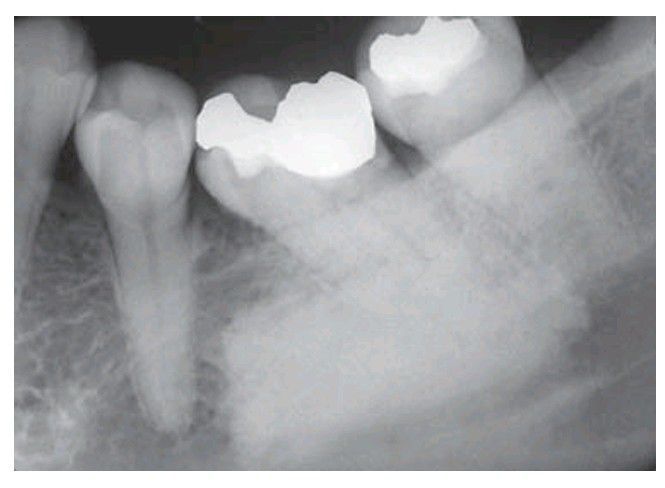

Sclerotic bone island in the posterior mandible, a relatively dense example. The periphery may be sharply or less well defi ned. Courtesy Mr EJ Whaites.